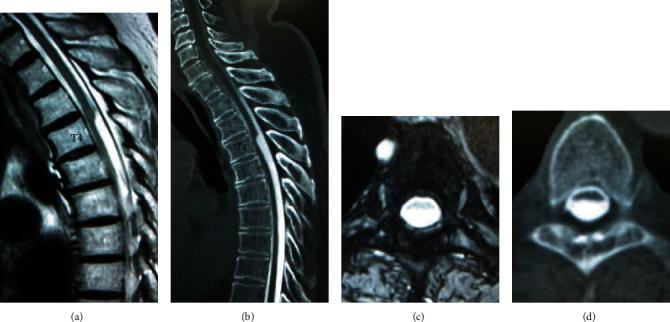

An arachnoid web (AW) is a relatively rare disease and shows clinical symptoms and radiological findings similar to those of an arachnoid cyst (AC) or spinal cord herniation (SCH). Since the operative procedures for an AW are generally different from those intrathecal disorders, correct preoperative differential diagnosis is important. The purposes of this study were to report the usefulness of magnetic resonance imaging (MRI) and computed tomography (CT) myelography for diagnosing AW and to show the histological findings and clinical results. Two patients, a 79-year-old man and a 43-year-old woman, are presented. The primary diagnoses were AC with ossification of the ligamentum flavum and epidural hematoma, respectively, in previous hospitals. They were finally diagnosed by the characteristic MRI and CT myelogram finding called the "scalpel sign." Histological findings showed epithelial cells and fibrous tissue derived from arachnoid tissues and microcalcifications. After surgery, the scalpel sign has vanished, and aggravation of their symptoms was prevented.

蛛网膜网(AW)是一种相对罕见的疾病,其临床症状和影像学表现与蛛网膜囊肿(AC)或脊髓疝(SCH)相似。由于AW的手术操作通常与鞘内疾病不同,因此术前进行准确的鉴别诊断很重要。本研究的目的是报告磁共振成像(MRI)和计算机断层扫描(CT)脊髓造影在诊断AW中的作用,并展示组织学检查结果和临床疗效。本文介绍了两名患者,一名79岁男性和一名43岁女性。在之前的医院中,他们最初的诊断分别为伴有黄韧带骨化的AC和硬膜外血肿。最终通过具有特征性的MRI和CT脊髓造影表现即“手术刀征”得以确诊。组织学检查结果显示有源自蛛网膜组织的上皮细胞、纤维组织和微钙化。手术后,“手术刀征”消失,且其症状加重得到了预防。